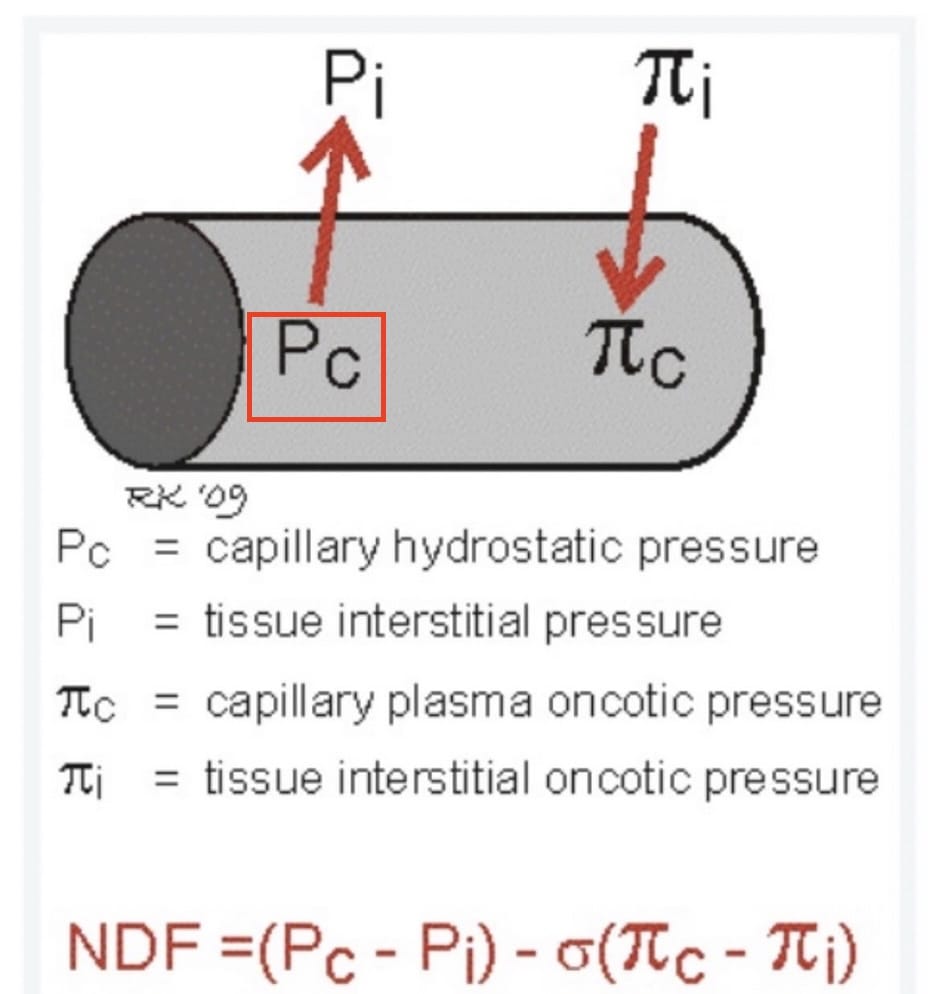

The Starling Equation describes the factors determining fluid filtration across the pulmonary capillary.

NDF represents the net driving force for fluid filtration

σ represents a reflection coefficient for movement of large molecules (such as protein) across the capillary wall - from 0 if completely permeable to 1 if impermeable.

The Starling Equation in the Lung

Source: https://www.anaesthesiamcq.com/FluidBook/fl4_4.php

Lung edema occurs when factors in the Starling Equation promote excessive capillary fluid filtration

We distinguish between hydrostatic and acute lung injury edema 1